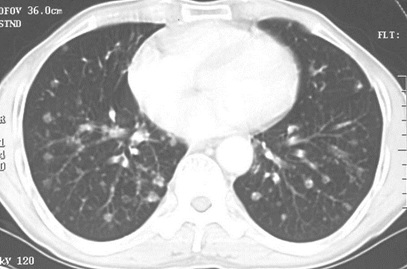

男性,55岁,结肠癌术后2年。(本题满分2.00分)

本题答案:D

题目解析:【该题针对“CT-肺癌”知识点进行考核】